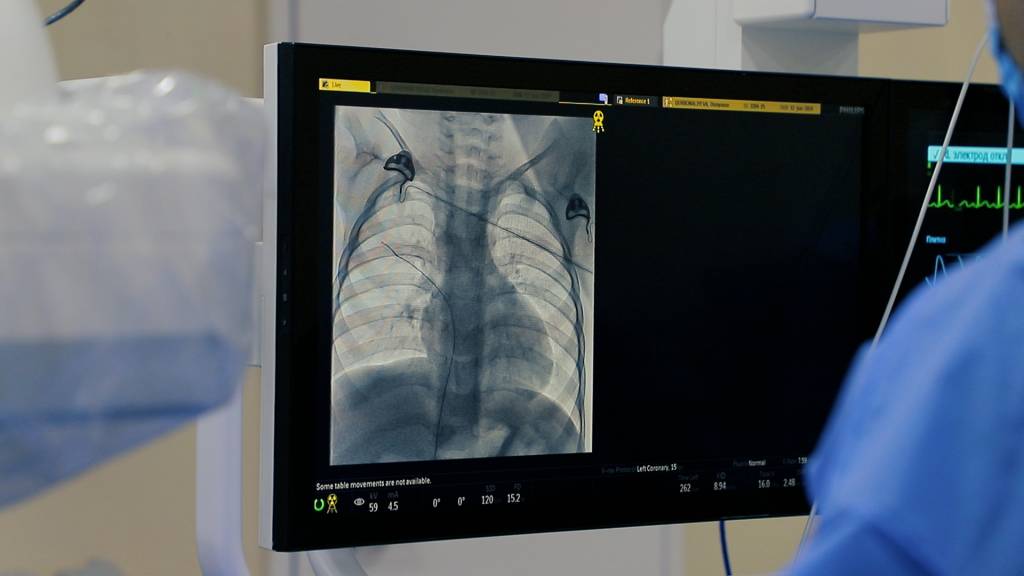

Kuni kecha 4 nafar yuragida tug‘ma nuqsoni bor bolalarda murakkab jarrohlik amaliyotlari o‘tkazildi. 3 nafarida yopiq, 1 nafarida esa ochiq usulda yurakdagi tug‘ma nuqson to‘liq bartaraf etildi. Bu xayrli ish Bolalar milliy tibbiyot markazining yuqori malakali shifokorlari bilan hamda viloyat Sog‘liqni saqlash boshqarmasi tasarrufidagi muassasalari xodimlari hamkorligida qilindi.

Tumandagi Gulzor mahallasida yashovchi Navbahor Qudratovaning kenja o‘g‘li hozir ikki yoshda. Afsuski u uch oyligida o‘tkazilgan tibbiy tekshiruvlarda yuragida teshigi borligi aniqlangan edi. Shundan buyon bolada muttasil ahvoli yomonlashavergan. Oila kattalari bolani bu ahvoli og‘irlashganini bilib tuman avval viloyat shifokorlariga keyin poytaxtga davolagani olib borgan. Aksiya doirasida bu ayolning o‘g‘li yuragida ham yopiq tibbiy amaliyot o‘tkazildi. Tez fursatda jarayonlar ijobiy tarzda yakunlandi.